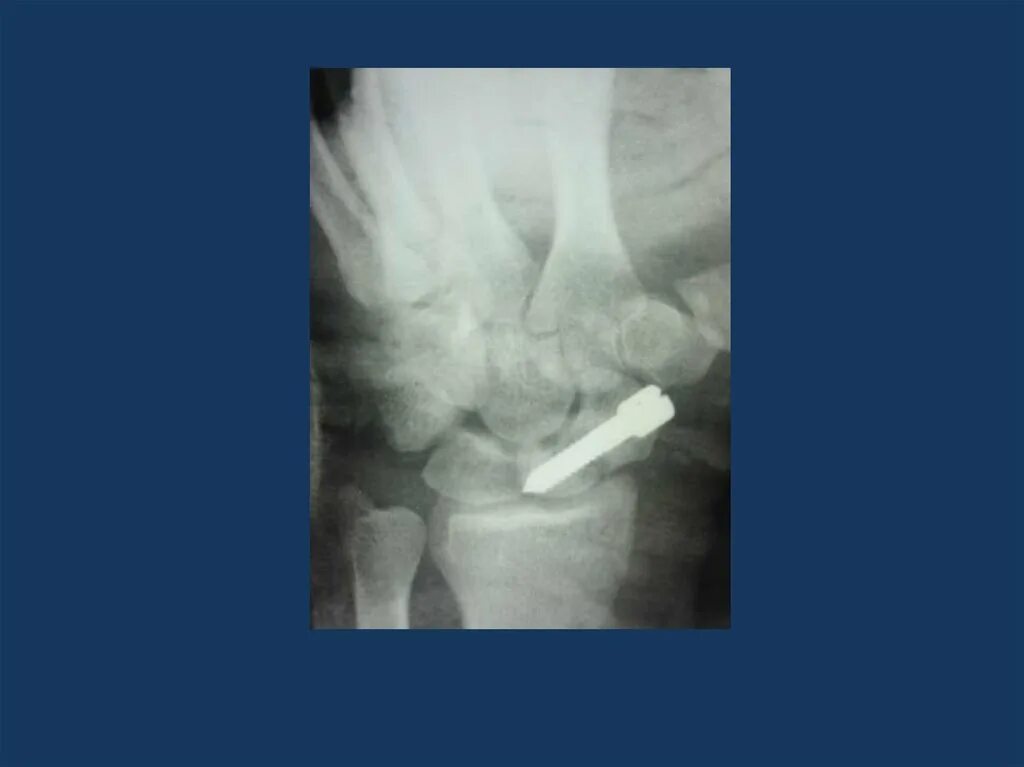

Полное расхождение суставных